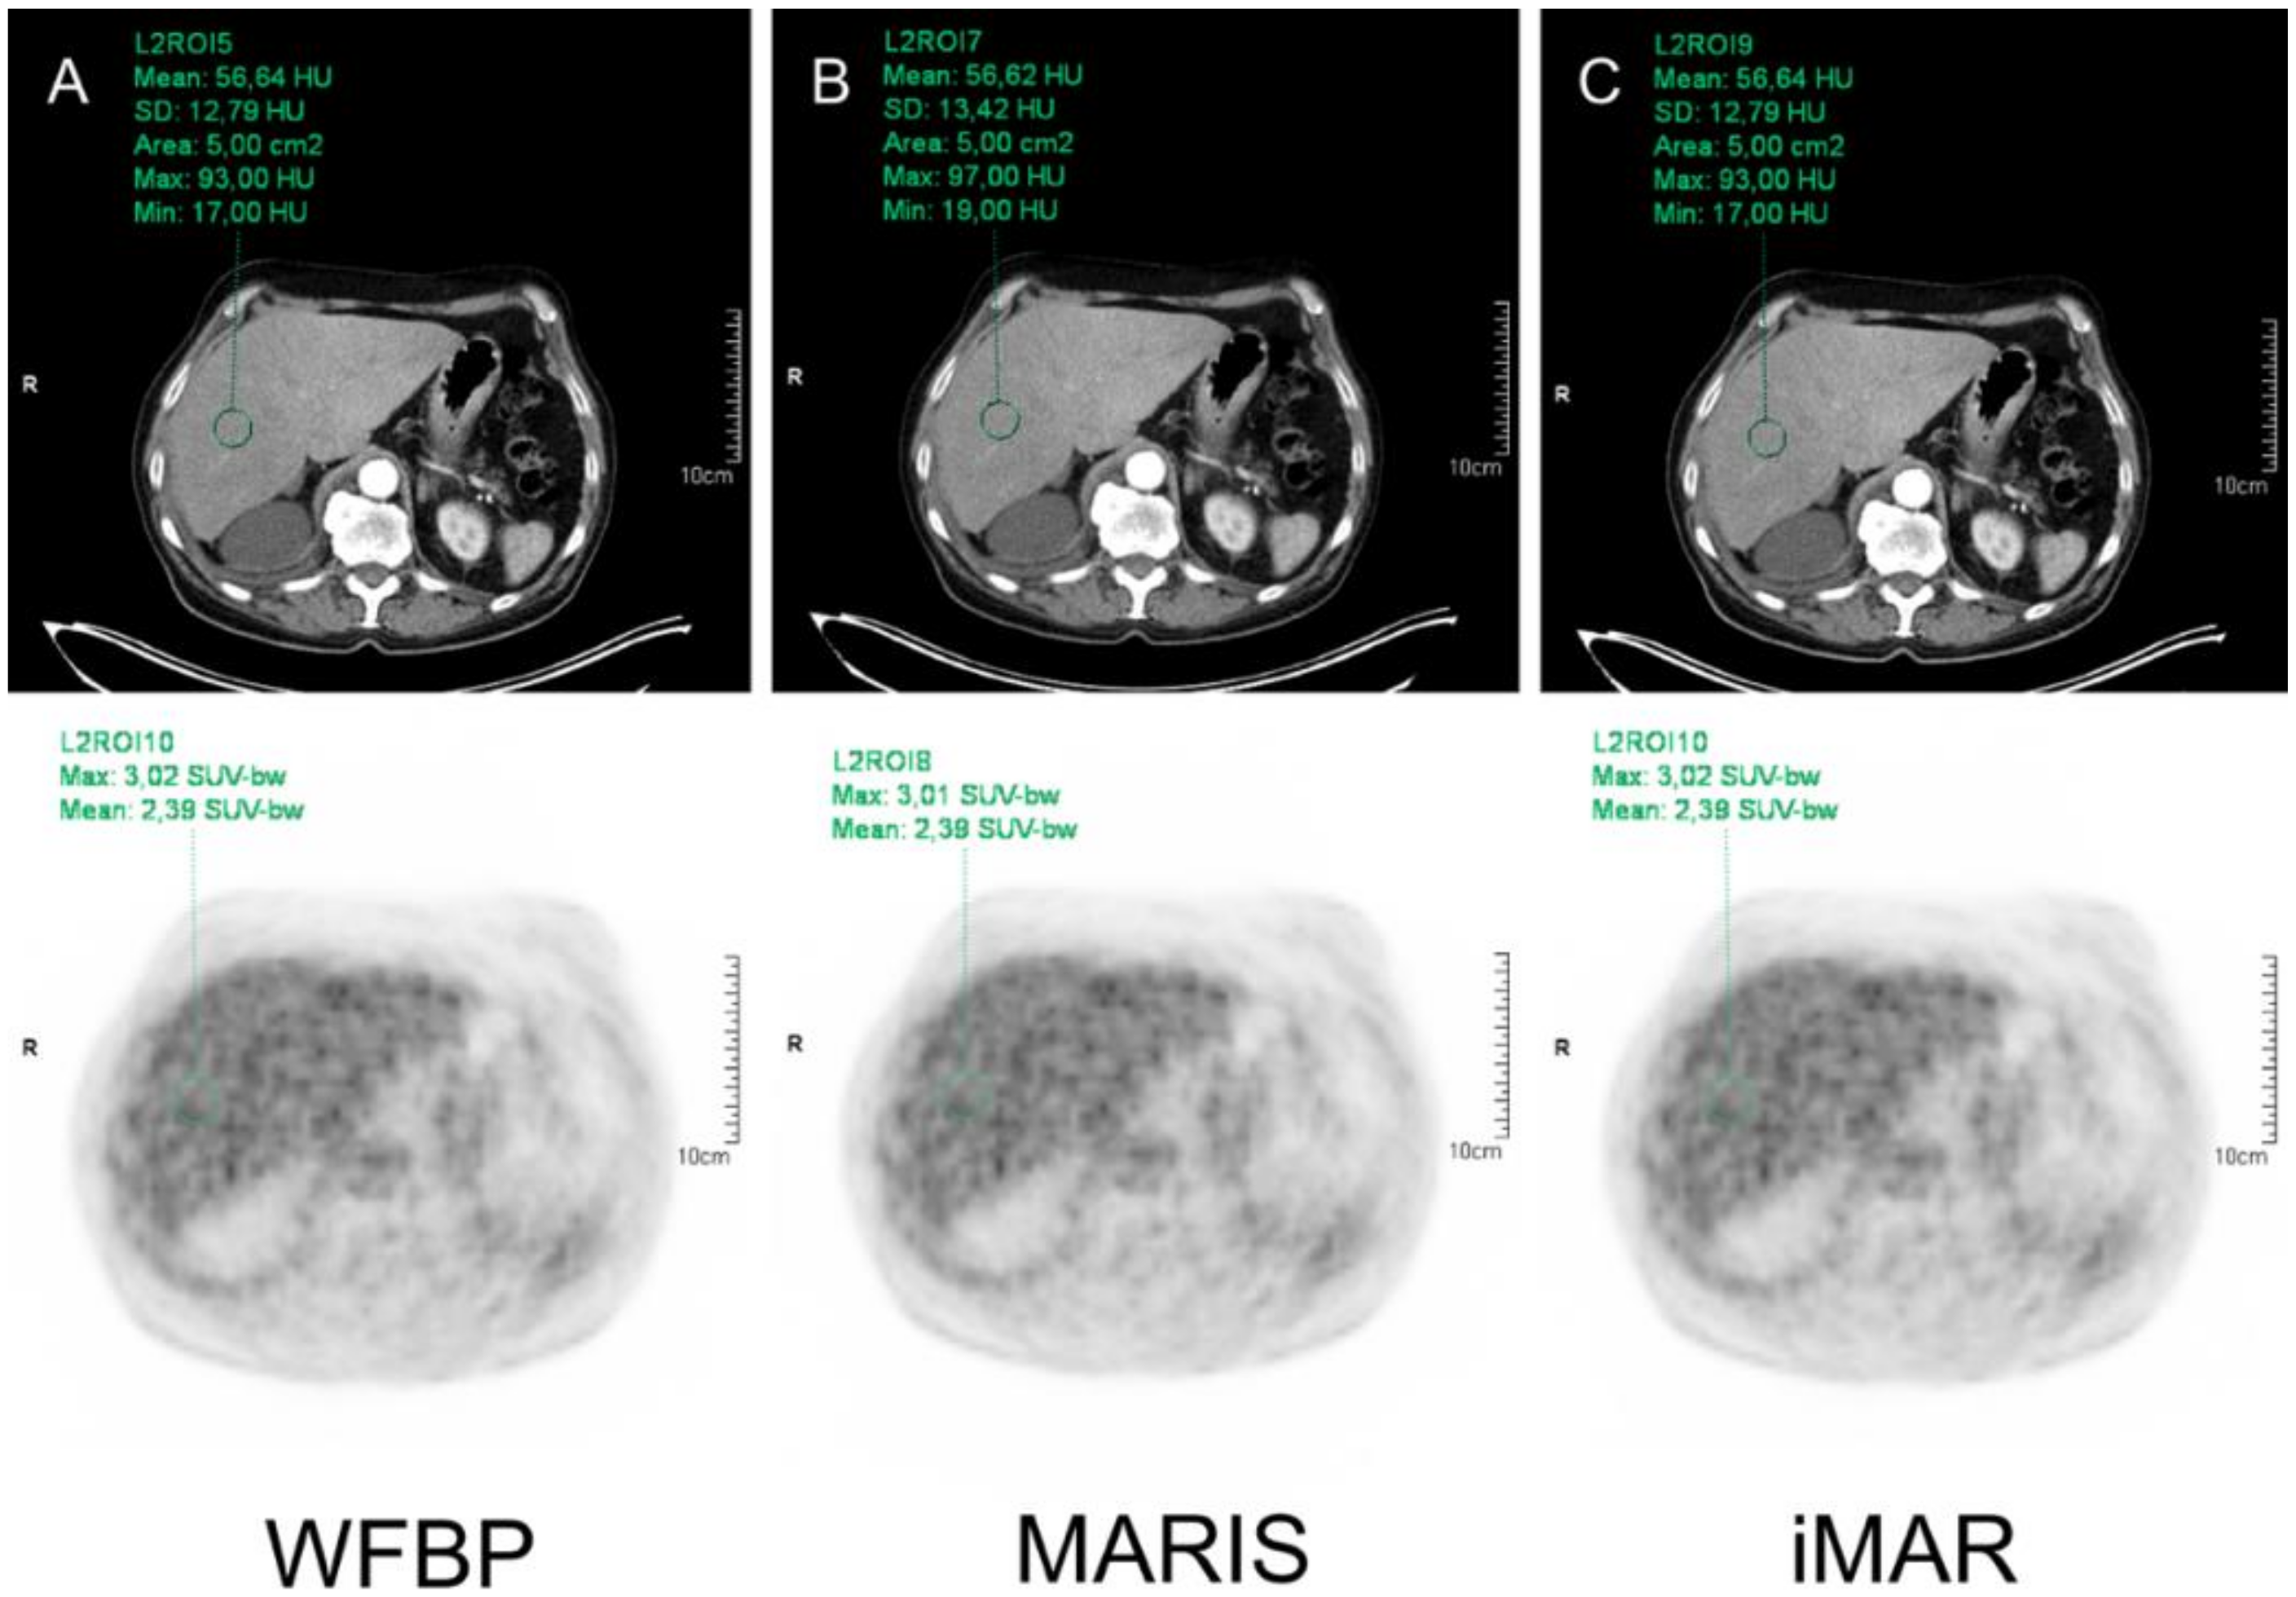

| WFBP | MARIS | iMAR | WFBP | MARIS | iMAR | WFBP | MARIS | iMAR | ||

| Liver | 82.72 ± 26.95 | 82.80 ± 26.94 | 82.69 ± 26.92 | 3.05 ± 0.61 | 3.04 ± 0.61 | 3.05 ± 0.61 | 2.41 ± 0.46 | 2.40 ± 0.46 | 2.41 ± 0.46 | |

| p-value | WFBP vs. MARIS | 0.295 | 0.095 | 0.353 | ||||||

| WFBP vs. iMAR | 0.055 | 0.568 | 0.159 | |||||||

| MARIS vs. iMAR | 0.157 | 0.084 | 0.278 | |||||||